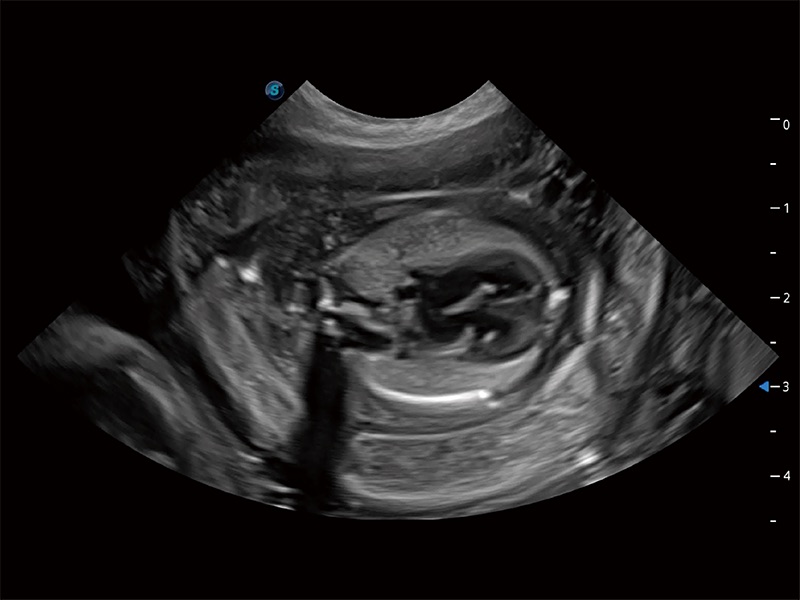

动物是人类最亲密的朋友和最值得信赖的伙伴。九州酷游也一直致力于探索动物专用的超声影像解决方案。全新推出的ProPet系列,是九州酷游在动物超声影像智能化、专业化、精准化的一次跨越式革新。动物不能用言语来表述自己的不适,通过超声影像,ProPet系列搭建了动物医生与不同物种沟通的“桥梁”,为动物医生注入了“治愈之力”。 ProPet 80 是九州酷游匠心打造的一款高端动物专用彩超,采用性能卓越的全新硬件架构,极大提升超声系统的运行效率和数据处理能力,帮助动物医生从容应对日益增多的挑战性病例和日益多样化的临床需求。

ProPet 80 专为动物医生设计,对不同的动物体型和生理结构作出了针对性的优化。通过动物影像专用软件,可满足个性化的应用需求,帮助动物医生获得更精确的诊断数据。

ProPet 80 全新的动物超声智能软件和丰富的探头群,为动物医生提供了高清晰度和精细分辨率的图像,无论在宠物、马科、畜牧还是实验室动物等应用中都可以轻松应对,为您的日常工作带来满意的体验。